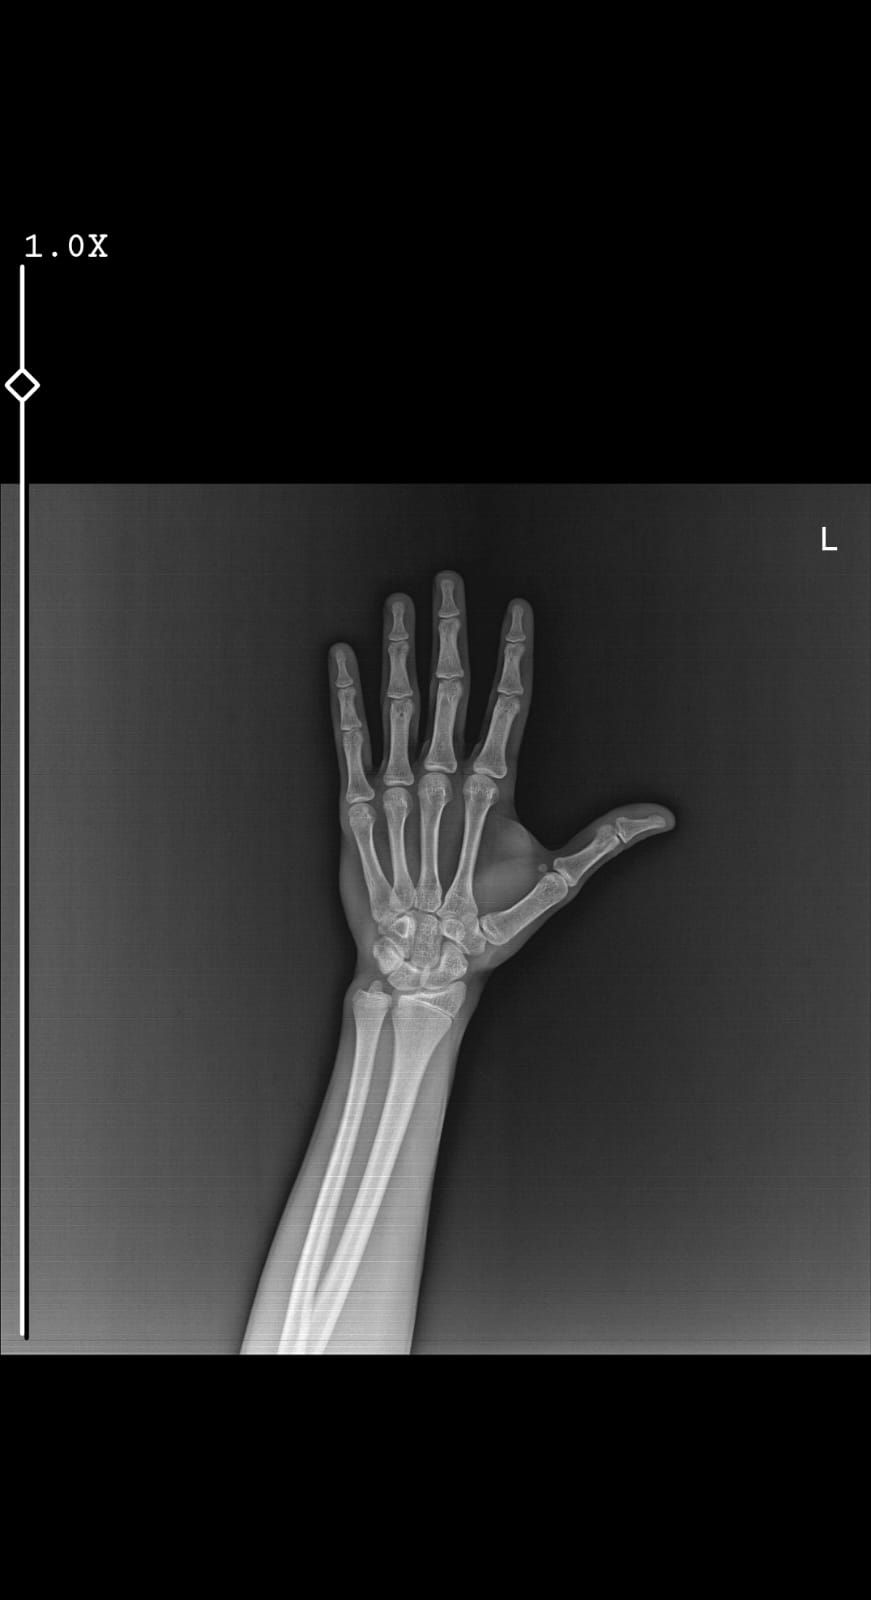

Öncelikle herkese merhaba, bugün kemik yaşıma baktırdım; doktor biyolojik yaşımın 13 yıl 9 ay kemik yaşımın 15 olduğunu, 2-3 cm daha uzayabileceğimi ve plakların kapanmak üzere olduğunu söyledi. Erken ergenliğe girmiş olabilir miyim, yüksek östrojenden dolayı mı kemik yaşım ileride diye sordum, hayır gelişimin gayet normal, erkeklerde zaten östrojen yok dedi. Ancak fazla testosterona sahipsen östrojene dönüşür (aromataz) diye de ekledi.

Röntgen:

Tüm bunlara karşılık daha uzayabilir miyim? Şimdiden konuyu ciddi cevaplayan herkese çok teşekkürler, iyi forumlar dilerim